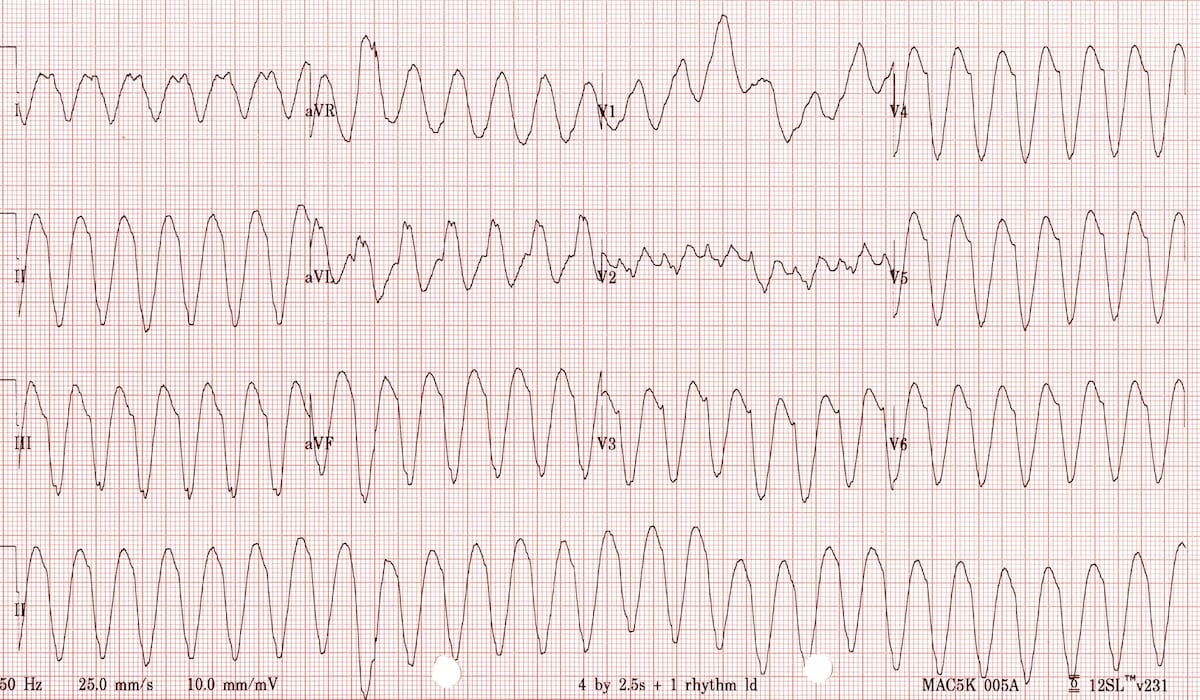

Usled različitih oboljenja srca, električna aktivnost srca može biti podražljiva i dovesti do izrazito visokog broja otkucaja srca (180-260/min) kada je ometeno funkcionisanje srca kao pumpe i ne dolazi do zadovoljavajuće ishrane tkiva i organa. Poremećaj ritma srca koji se zove komorska tahikardija (komorsko lepršanje) je stanje koje bolesnici u određenoj meri mogu da tolerišu ali im je neophodna hitna medicinska pomoć. Ovo stanje može da preraste u komorsku fibrilaciju, tzv „komorsko treperenje“ kada srce kao pumpa praktično ne funkcioniše i u osnovi ovo stanje je uzrokom nagle srčane smrti ukoliko se takav bolesnik ne reanimira i tretira elektrošokom.

Kardioverterdefibrilator ove tahiaritmije prepoznaje, posebnim algoritmima ih odvaja od ostalih tahikardija (ubrzan rad srca) koje nisu životno ugrožavajuće.

Prekida ih na dva načina:

- elektrostimulacijom (antitahikardni pejsing) koju bolesnik ne oseća, (ima samo simptome same tahikardije, osećaj ubrzanog rada srca, nedostatak vazduha, nesvesticu)

- i elektrošokom koji bolesnik oseća kao snažan udarac u grudi